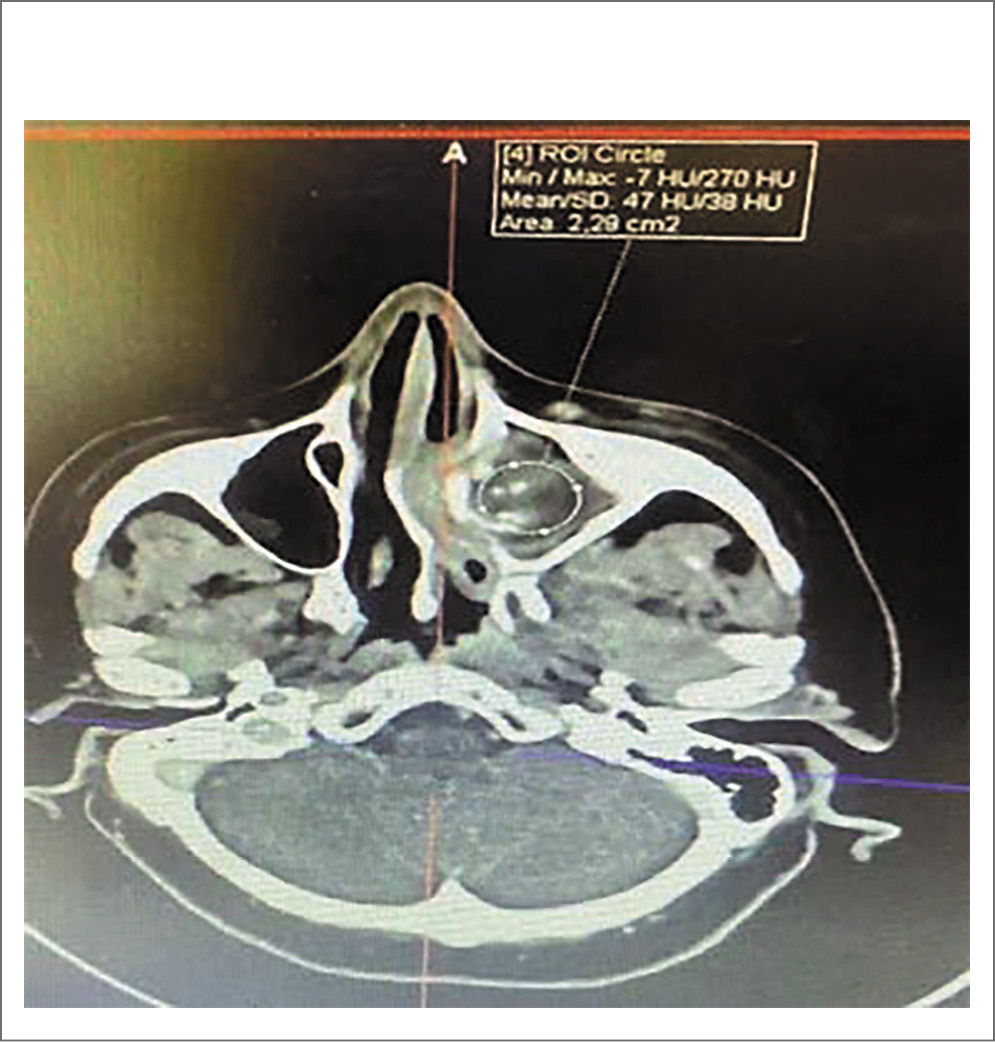

После эндоскопической визуализации полости носа и регистрации слева полипозных вегетаций с характерной окраской и консистенцией, обильным выделением густого слизистого секрета (рис. 2) и предыдущей КТ носа и ОНП пациентке выполнена МСКТ с контрастным усилением, заключение: тотальное затемнение левой гайморовой пазухи, клеток решетчатого лабиринта с разрушением медиальной стенки ВП и проникновением в полости носа, смещение носовой перегородки и компрессия средней носовой раковины, наличие группы гиперденсивных включений округлой формы, контраст не накапливается (рис. 3). После выставления диагноза левостороннего хронического ПРС, мицетомы гайморовой пазухи и проведения соответствующей предоперационной подготовки пациентке выполнена гайморотомия по Колдуэлл–Люку, этмоидотомия слева. Отмечено в левой ВП наличие органических субстратов высокой плотности. Интраоперационно взятые подозрительные фрагменты поврежденных тканей направлены на гистологическое исследование с соответствующим диагнозом (рис. 4).

Рис. 3. Контрастное усиление. Аксиальная проекция.